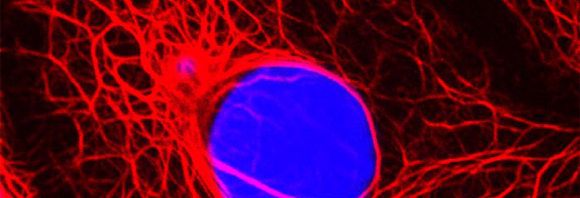

Auf die Kraft des eigenen Körpers statt beschleunigter Teilchen, setzen Forschungsansätze, die sich des körpereigenen Immunsystems zur Krebsbehandlung bedienen. Die Forschergruppen der Helmholtz-Allianz zur Immuntherapie bei Krebserkrankungen untersuchen, mit welchen Mitteln körpereigene Abwehrkräfte gegen Tumorzellen mobilisiert werden können. Denn grundsätzlich kann das menschliche Immunsystem Krebszellen als solche erkennen und bekämpfen, sofern diese sich ausreichen von gesunden Zellen unterscheiden. Da dies jedoch nur selten der Fall ist, bildet der Körper bei den meisten Krebserkrankungen keine eigenen, spezifischen Antikörper.

Insbesondere für krebskranke Kinder kann die immuntherapeutische Krebsbehandlung positive Wirkung erzielen. Denn Leukämiezellen sind für eine Immuntherapie gut zugänglich und Leukämie ist die häufigste Krebsform, an der Kinder erkranken. Problematisch in der Behandlung von Leukämien ist allerdings die Resistenz der Tumorzellen gegen den durch Chemo- oder Immuntherapie ausgelösten Zelltod (Apoptose). Hier setzt einer der Forschungsschwerpunkte der Wissenschaftler der Helmholtz-Allianz an: es sollen neue Kombinationstherapien entwickelt werden, die die Resistenz überwinden können.

Die Erforschung von Immuntherapien ist also noch nicht so weit, dass damit weitreichende und exklusive Heilungserfolge erzielt werden konnten. Dennoch sind sie bereits eine vielversprechende Ergänzung zu den klassischen Therapieformen. Professor Peter Krammer, Leiter der Abteilung Immungenetik am Deutschen Krebsforschungszentrum, wählt ein deutliches Bild, um seine Arbeit auch Laien verständlich zu machen: Er bezeichnet Antigene als „scharfe Kampfhunde, die allerdings noch nicht richtig von der Leine gelassen wurden“. Das Ziel der Forschung sei damit klar: „Wir müssen nur herausfinden, wie wir diese Kampfhunde richtig abrichten, damit sie an der richtigen Stelle zubeißen.“